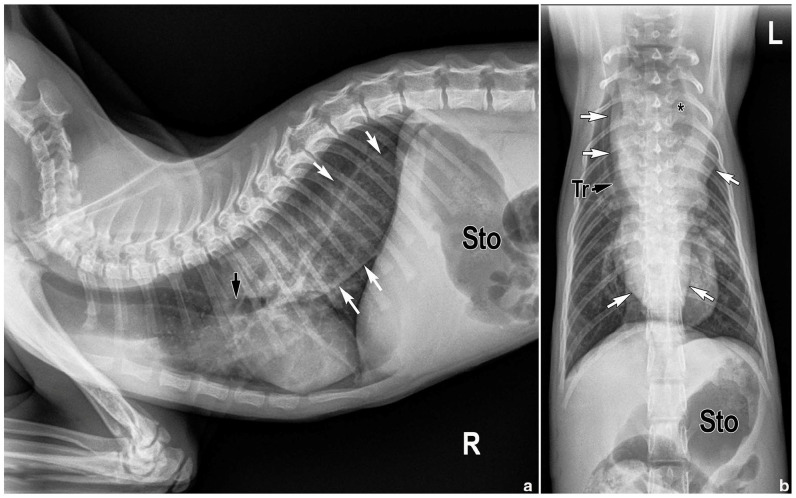

病例总结:猫食道肥大(ME)是一种罕见的食道运动障碍,会导致猫的反流、体重减轻,有时甚至死亡。它已被确定为继发于神经和神经肌肉疾病、食道机械性梗阻(如血管环异常、食道狭窄)和上气道梗阻等;当找不到病因时,被认为是特发性的。视频透视吞咽研究(VFSSs),特别是使用不受约束的自由喂养方案,尚未充分用于对反流猫的综合评估,包括确定ME的病因。在本病例报告中,一只3个月大的雄性完整家养短毛猫,自断奶以来有反流史,影像学证据显示为ME,其VFSS特征与食管下括约肌(LES)功能性梗阻相一致,符合LES贲门贲门样综合征。用药西地那非未能改善临床症状,采用Heller肌切开术和Dor底襞术矫正LES贲门失弛缓症的手术治疗被拒绝。由于护理人员对持续反流的同情疲劳,选择了安乐死。相关性和新信息:视频透视记录的LES功能性梗阻(即LES贲门亚样综合征)可以识别猫ME的新病因。建议使用自由喂养不受约束的VFSS方案,对吞咽障碍进行生理评估,且不存在比在家进食和饮水更高的误吸风险。对LES贲门弛缓样综合征的认识可能会导致针对功能性阻塞的定向治疗的进一步研究,正如已经在人类和狗身上进行的那样。

Case summary: Feline megaesophagus (ME) is a rare failure of esophageal motility leading to regurgitation, weight loss and sometimes death in cats. It has been identified secondarily to neurologic and neuromuscular disorders, mechanical obstruction of the esophagus (eg, vascular ring anomalies, esophageal stricture) and upper airway obstruction among others; when no cause is found, it is considered idiopathic. Videofluoroscopic swallow studies (VFSSs), especially using an unrestrained free-feeding protocol, are underutilized for comprehensive evaluation of cats with regurgitation, including identifying the etiology of ME. In this case report, a 3-month-old male intact domestic shorthair cat with a history of regurgitation since weaning and radiographic evidence of ME had VFSS features compatible with a functional obstruction of the lower esophageal sphincter (LES) consistent with LES achalasia-like syndrome. Medical management with sildenafil failed to improve clinical signs, and surgical correction of LES achalasia using a Heller myotomy and Dor fundoplication was declined. As a result of caregiver compassion fatigue from persistent regurgitation, euthanasia was elected.